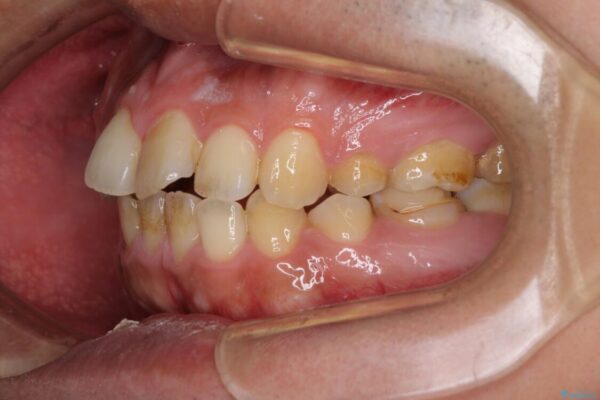

高校時代に行った抜歯矯正が後戻りをしたとのことで来院された患者様です。

再矯正であることから、目立ちにくい装置を希望されたため、インビザラインにて矯正治療を行うこととしました。

下顎骨が左側に変位しているため、正中が合わないことは予想できましたが、歯列が整った後も咬み合わせが安定せず、咬み合わせを落ち着かせるために1年以上の期間を要しました。

治療前

• 後戻りでデコボコの前歯 インビザライン矯正治療 治療前画像